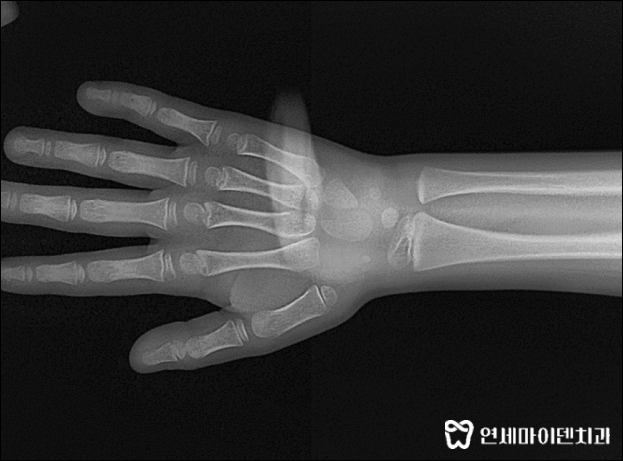

어린이 치아교정 진단 시에는 수완부 방사선을 촬영하여

성장판 평가도 빼놓을 수 없습니다.

성장기이기 때문에 성장판이 어느정도 열렸는지,

치아교정 기간과 시기를 결정하는데 중요한 역할을 합니다.

이 환자분은 아직 나이가 많이 어리고

유치가 영구치로 교체되는 과정에서 불편함을 느끼면

아래턱을 일부러 틀어서 내밀어 무는 안 좋은 습관이 생길 수 있기 때문에

일찍 교정을 시작하는게 좋다고 판단했고

최대한 빨리 교정치료를 진행하는 것으로 치료 계획을 세웠습니다.